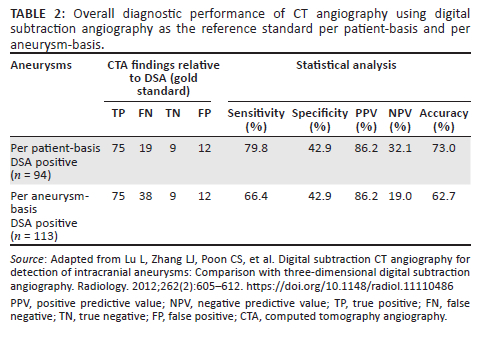

A total of 115 patients were included in this study, aged between 19 and 83 years (mean: 46 years ± 13.3), with the majority in the 41-50 and 51-60-year age groups (Table 1). The female to male ratio was 1.5:1 (Table 1). Digital subtraction angiography detected ruptured aneurysms in 94 of 115 patients. Fourteen of the 94 patients (15%) had multiple aneurysms. Of the 14 patients, 10 patients had one additional aneurysm, three patients had two aneurysms and one patient had three additional aneurysms. In total, DSA detected 113 ruptured and unruptured aneurysms in 94 patients. Therefore, 94 aneurysms per patient-basis and 113 aneurysms per aneurysm-basis were detected by the gold standard (DSA) (Table 2). No identifiable cause of SAH was found in 21 patients (18%).

Overall CT angiography diagnostic performance

CT angiography correctly identified 75 of 94 (80%) and missed 19 of 94 (20%) ruptured aneurysms per patient-bases. The detailed diagnostic performance of CTA per patient-basis is demonstrated in Table 2. Computed tomography angiography missed all 19 incidental, non-causative aneurysms in 14 patients with multiple aneurysms on DSA, resulting in a higher false negative (FN) finding of 38 aneurysms. Thus, the diagnostic performance of CTA per aneurysm-basis was poor, with a decreased sensitivity and accuracy of 66% and 63%, respectively.

In this single, tertiary institution study we retrospectively evaluated the diagnostic accuracy of CTA for detecting ruptured intracranial aneurysms using DSA as a reference standard. The CTA diagnostic performance was limited, with sensitivity, specificity, PPV, NPV and accuracy of 80%, 43%, 86%, 32% and 73%, respectively. The CTA diagnostic efficiency was even lower for multiple aneurysms because of failure to detect all additional, non-causative aneurysms. Very small aneurysms with diameters < 3 mm were difficult to detect on CTA (sensitivity of 30%), while there was a drastic improvement in sensitivity for aneurysms ≥ 3 mm with sensitivities from 81.5%. There was no significant difference between the CTA sensitivity for anterior versus posterior circulation aneurysms, even though the vast majority of aneurysms were located in the anterior circulation. Aneurysms arising from PComm were difficult to detect on CTA (sensitivity of 56%), whereas CTA sensitivity was not adversely affected in the rest of the major anterior circulation locations, namely anterior communicating artery (AComm), anterior cerebral artery (ACA), middle cerebral artery (MCA) and internal carotid artery (ICA).

Good CTA performance reported in the literature may be because of optimal reading conditions by at least two experienced neuro-radiologists reading CTA and DSA images either individually or in consensus11,12,13,17 and consistent use of post processing tools and techniques. Some studies used a probability scale for the level of confidence in diagnosing the aneurysms on CTA.10,17 Contrasting this, few previous studies showed limited overall CTA diagnostic performance14,15 similar to this study. Compromise in CTA sensitivity was demonstrated for multiple, incidental aneurysms in this study, congruent to several studies.15,17 The low NPV (32%) in this study depicts CTA as a suboptimal screening test, similar to Philip et al. (50%)14 but contrary to most studies that demonstrated NPVs of 91% and higher.11,16,17